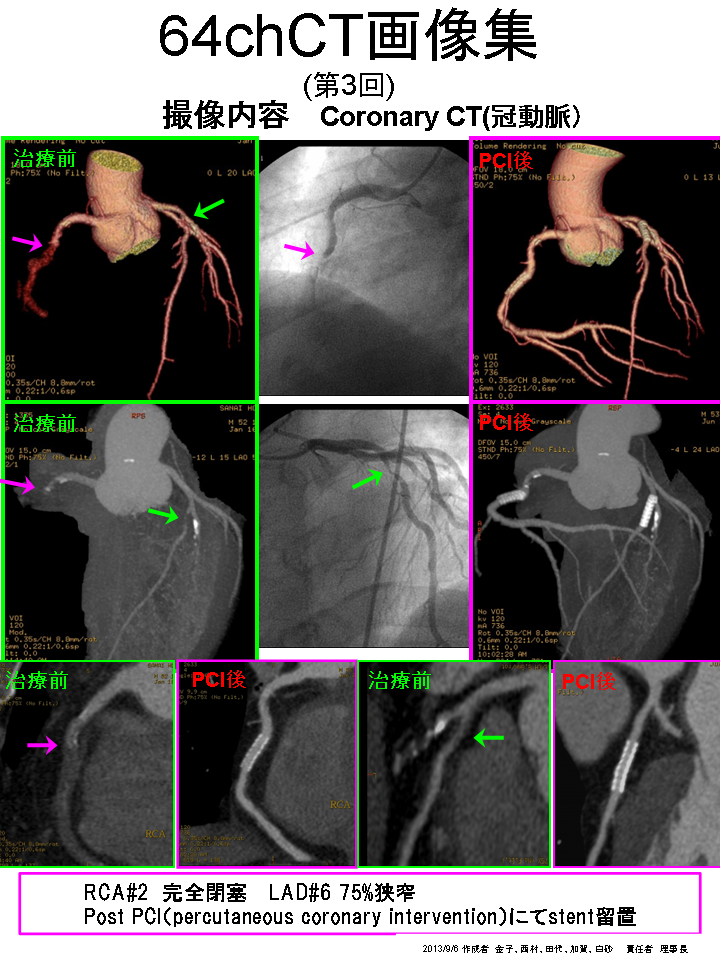

このボリュームCTにより早期発見から早期治療へつなげることが可能となり、心臓カテーテル検査の代替としても期待されます。

一部の症例以外では、従来の心臓カテーテル検査なしに血管狭窄の評価が可能であり、万が一、心筋梗塞になられた場合でも治療後の経過観察の心臓カテーテル検査は不要となります。

①安定した心臓撮影 : 心臓を5秒にて撮影(従来のマルチスライスCTでは約20秒間撮影)